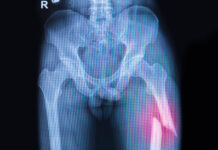

Particolarmente frequente negli anziani, a causa dell’osteoporosi, e negli sportivi, la frattura di radio distale, anche detta frattura di polso, è tra le più comuni soprattutto dopo i 50 anni. La letteratura ci dice, inoltre, che questa frattura è più frequente nelle donne.

Una parte dei pazienti con frattura di polso deve essere sottoposta a un intervento chirurgico di fissazione con placca volare, eseguita in aperto, che richiede una immobilizzazione dell’articolazione della durata di 2-3 settimane.